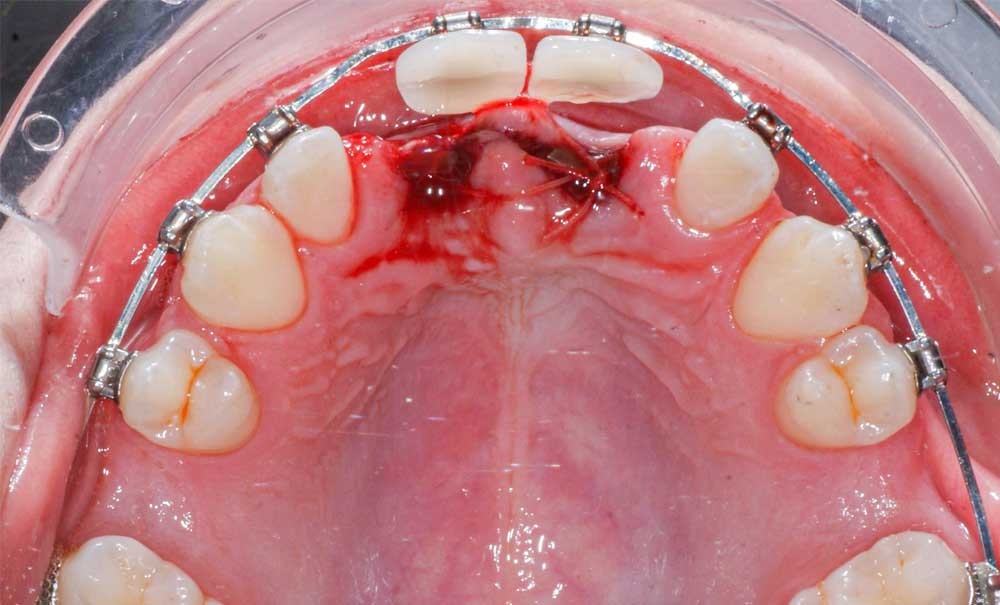

L’auto-transplantation est une méthode chirurgicale dans laquelle une dent est repositionnée chez le même patient, dans un autre site. Elle nécessite une prise en charge multidisciplinaire. Le respect de certaines conditions permet de garantir le maintien du volume osseux alvéolaire grâce à la préservation du ligament parodontal, sa stimulation physiologique, voire sa régénération.

L’auto-transplantation dentaire peut être réalisée avec succès dans la région antérieure et postérieure de la denture. Cet article se concentrera sur la zone antérieure.

L’auto-transplantation peut être envisagée chez un jeune patient en pleine croissance dans plusieurs situations, notamment dans le cas de dents manquantes ou compromises à la suite d’un traumatisme, d’anomalies de forme ou d’éruption, ou en raison d’une agénésie. Elle doit être réservée à un patient dont l’état général est bon.